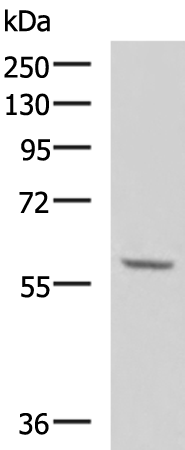

分类: 科研抗体货号: P10778别名: SGS; SKV应用: WB,IHC反应种属: Human, Mouse